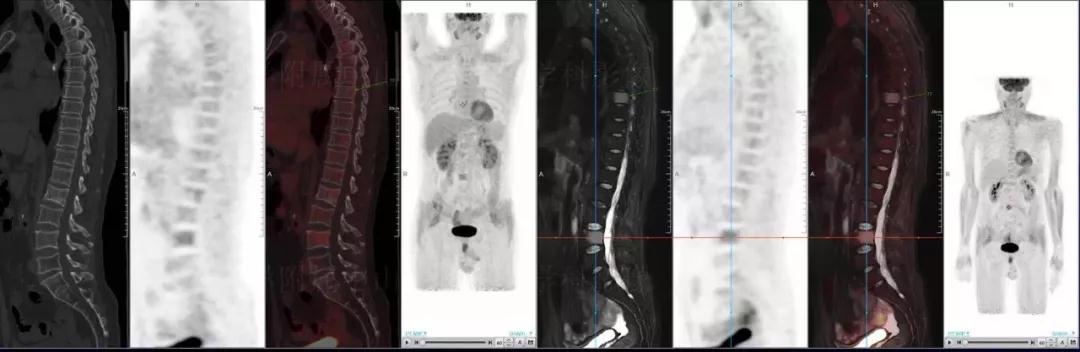

(男性,53歲。確診多發(fā)性骨髓瘤10月。經(jīng)過7周期VCD方案化療后,現(xiàn)行療效評價(jià)。)